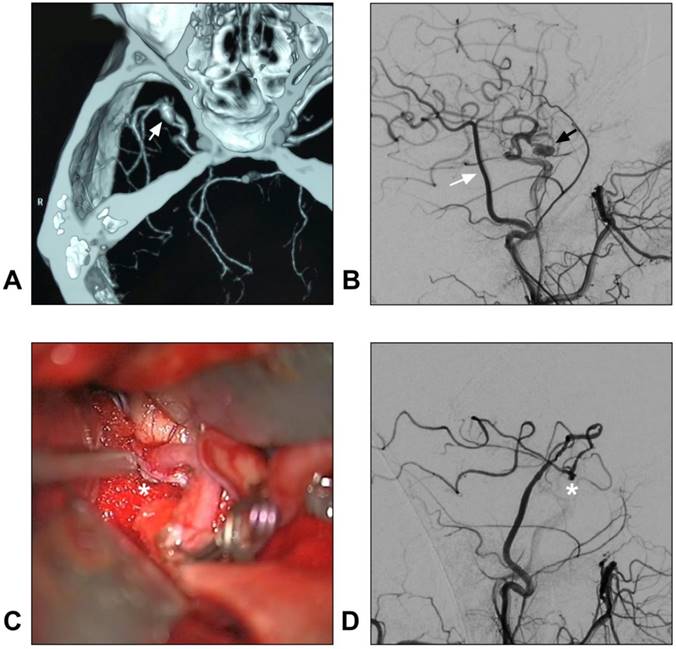

Figure 4

STA-MCA bypass for intracranial aneurysm. A: CTA reveals a dissecting aneurysm on the trunk of the MCA (arrow); B: DSA of the CCA shows the STA (white arrow) and aneurysm (black arrow); C: An end-to-side anastomosis between the STA and MCA trunk (asterisk) is performed; D: Postoperative angiogram of the ECA shows the STA-MCA bypass (asterisk) is patent. Abbreviations: CCA: common carotid artery; CTA: computed tomography angiography; DSA: digital subtraction angiography; ECA: external carotid artery; MCA: middle cerebral artery; STA: superficial temporal artery.

In addition, with a larger caliber, the STA trunk can provide more blood flow than the distal STA branches do. Hence, STA trunk-to-M2 of MCA or proximal PCA high-flow bypass with a short radial artery interposition graft should not be forgotten as it represents an excellent bypass to add to the armamentarium of choices when considering bypass options for complex aneurysms [80, 81]. A typical case of an aneurysm treated with STA-MCA bypass is described in Figure 4.